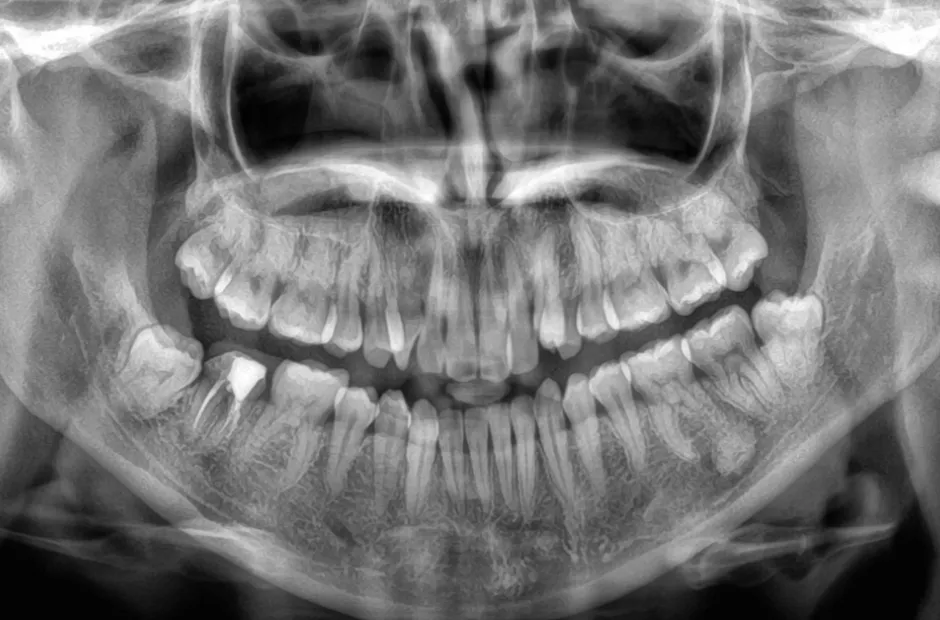

叢生

| 診断名・主訴 | 叢生 |

|---|---|

| 年齢・性別 | 43歳・女性 |

| 治療期間・回数 | 2年7か月 27回 |

| 治療に用いた主な装置 | 舌側矯正 |

| 抜歯部位 | 両顎4,4 |

| 治療費 | 100万円(税抜) |

| リスク・副作用 | 装置による違和感・疼痛・歯肉退縮・歯根吸収・虫歯のリスクなど |

治療前

治療中

治療後